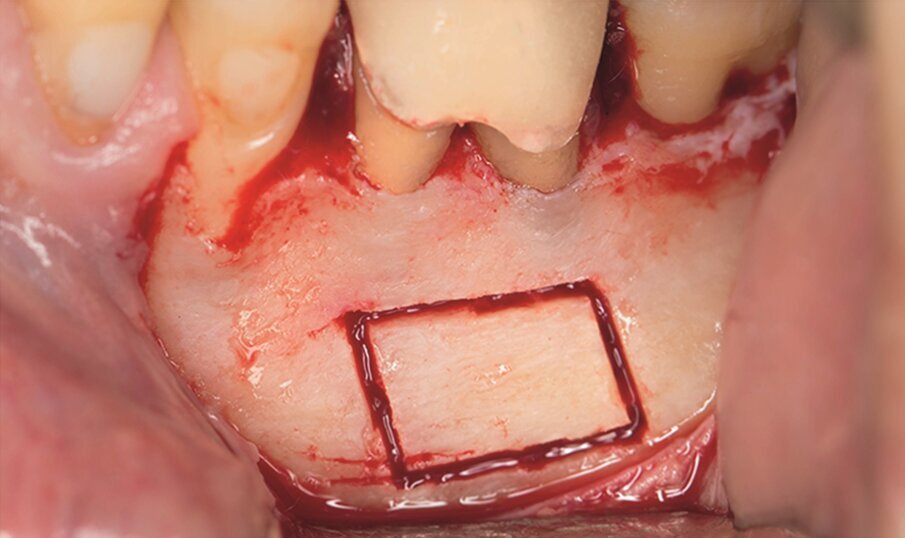

Fig. 1e–i: During microsurgery, the template was adjusted (e), …

… the limits of the cortical window were marked in the bone (f) …

… with a saw mounted in a Piezotome CUBE LED handpiece, then the bone was cut and removed (g & h) …

… to access the apical area and perform the apicectomy, apical cavity preparation and retro-filling of the mesial and distal roots (i).